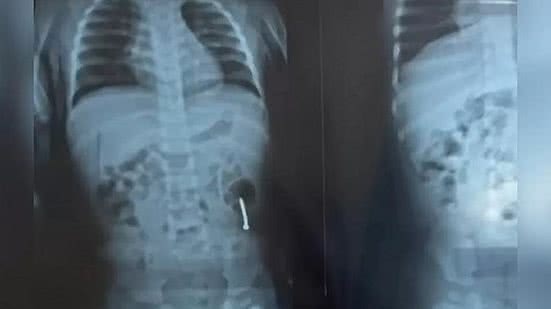

Uma menina de um ano foi socorrida a uma unidade de saúde de Marabá (PA) após engolir um prego no dia da própria festa de aniversário. Ela passou quatro dias internada e precisou ser transferida para um hospital regional do município.

Houve uma tentativa de remoção por endoscopia, mas o prego desceu para o intestino e foi necessário avaliar o quadro. Ontem, a menina foi encaminhada ao Hospital Regional de Marabá, onde um novo raio x detectou que o objeto estaria descendo "de cabeça para baixo", o que facilitaria a saída e diminuiria as chances de perfuração.